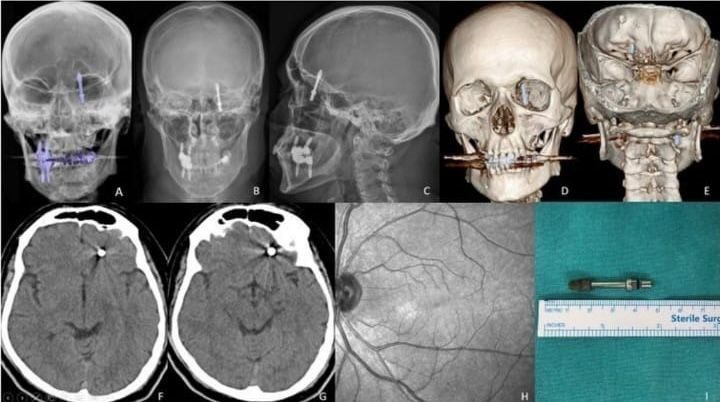

Nilüfer ilçesinde özel bir diş kliniğinde muayene olan Yılmaz’a, dişlerinin sallandığı gerekçesiyle implant tedavisi önerildi. Ancak iddiaya göre, doktor A.D.’nin hatalı müdahalesi sonucu implant vidası çene kemiğini delip kafatasına saplandı.

Baygınlık geçiren Yılmaz, kliniğin kendi aracıyla hastaneye kaldırıldı. Tomografi çekiminde vidanın beynine kadar ilerlediği ortaya çıktı. Acil ameliyata alınan talihsiz adam, saatler süren operasyonla ölümden döndü.